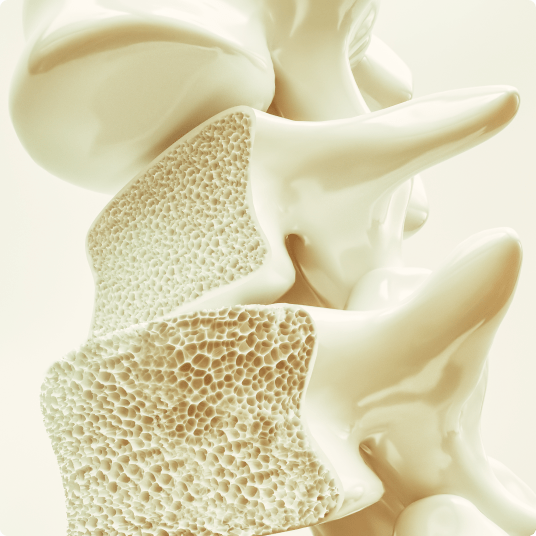

bone density

What Is A Bone Density Test?

A bone density test uses advanced CT scanning technology to measure the amount of bone mineral in specific areas of your skeleton. This non-invasive test helps determine if you have, or are at risk for, osteoporosis—a condition that makes bones fragile and more likely to break.

Our CT scanner generates precise images of your bones, particularly focusing on areas most prone to fractures, such as the spine and hip.